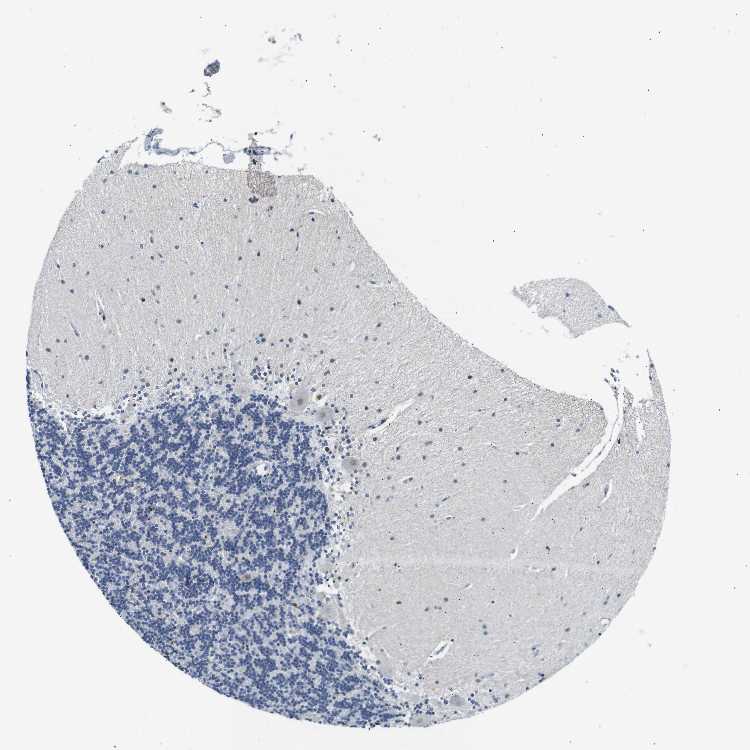

CEREBELLUM - Antibody stainingi

Antibody staining in the annotated cell types in the current human tissue is reported as not detected, low, medium, or high, based on conventional immunohistochemistry profiling in selected tissues. This score is based on the combination of the staining intensity and fraction of stained cells.

Each image is clickable and will lead to virtual microscopy that enables deeper exploration of all samples and also displays staining intensity scores, fraction scores and subcellular localization as well as patient and tissue information for each sample.

Antibody HPA002267Antibody HPA002531Antibody CAB013480

Purkinje cells Not detectedHighMedium

Cells in granular layer Not detectedLowMedium

Cells in molecular layer Not detectedHighLow